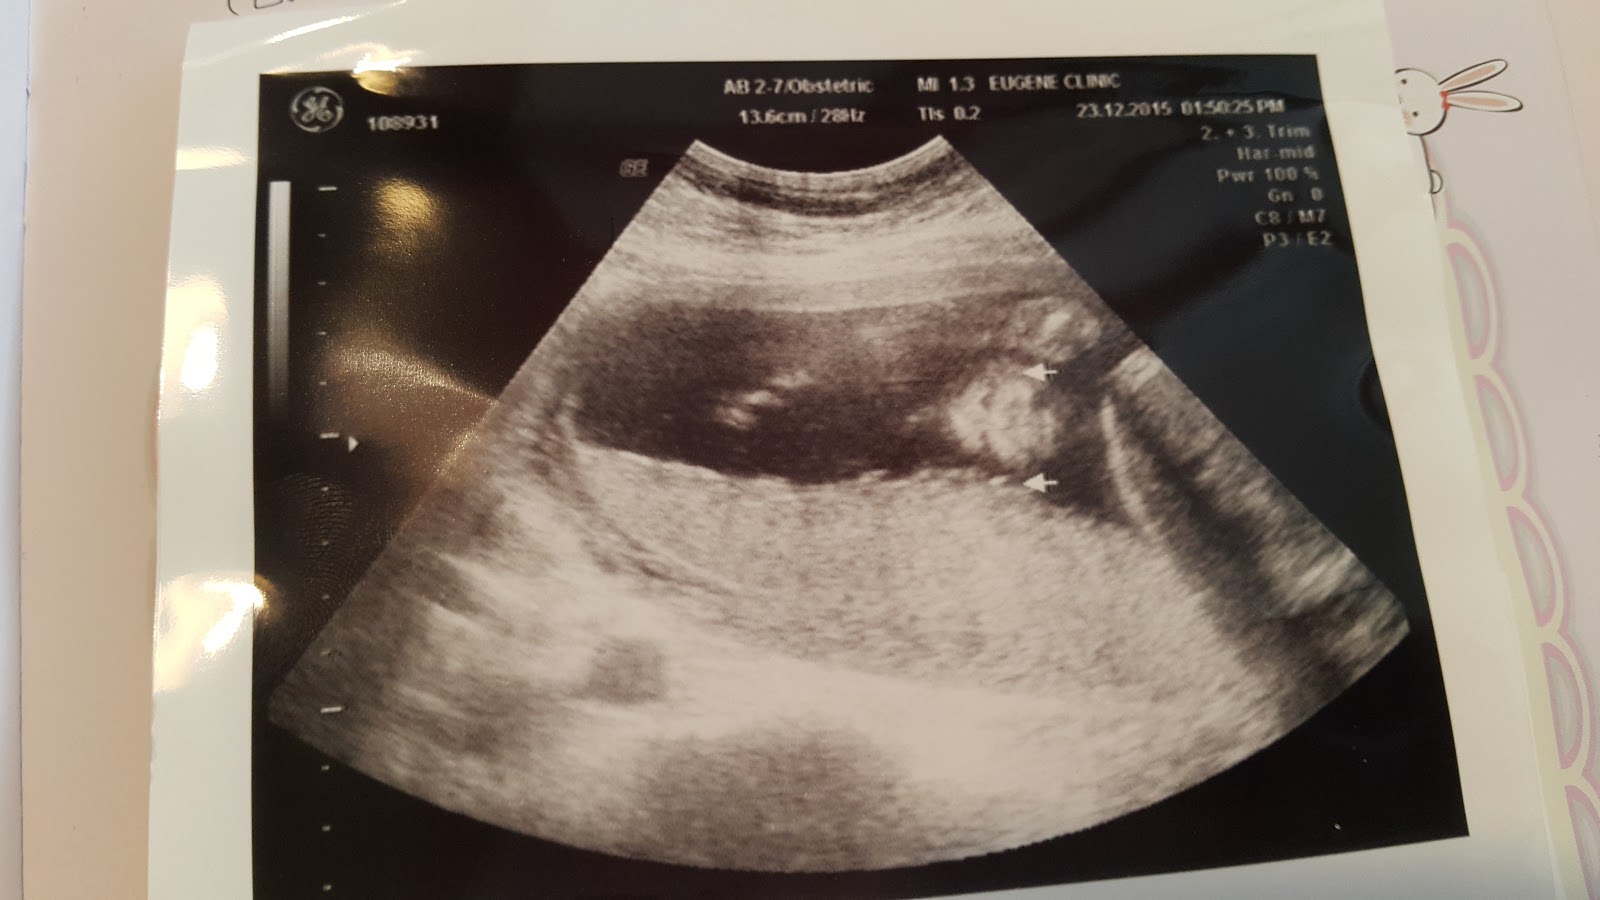

做高層次超音波主要是看清楚寶寶從頭到腳的器官

時間會比較久,也需要另外收費,大部份都是在20w-24w做高層次超音波

第一張照片應該是嘴巴吧!

醫生邊照會告訴你大約怎麼看,嘴色主要是看有沒有兔唇

還好寶寶沒有兔唇,上次產檢時醫生已經先看過了,所以這個部位是沒有問題的

我怎麼覺得寶寶的嘴唇有點厚,當時哥哥也是這樣,超音波照片裡的嘴巴都超厚的